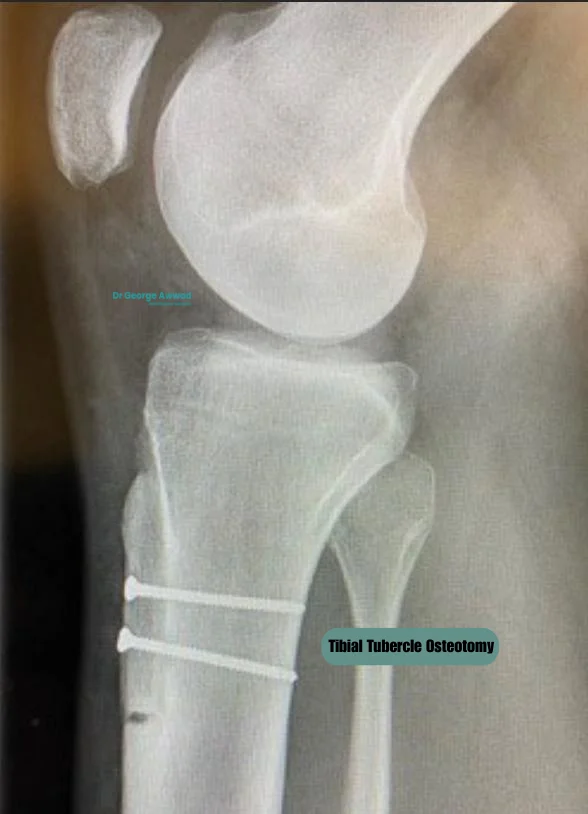

• Tibial Tubercle Osteotomy

Tibial Tubercle Osteotomy